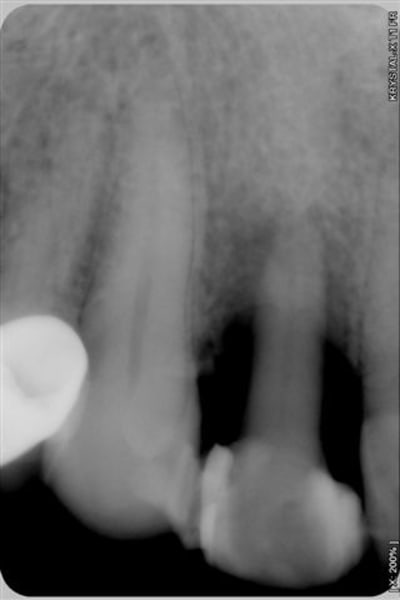

patient revu le 25 aout pour biostimulation, 4ème radio prise lors de la séance montre un début de régénération osseuse.

La 5ème radio prise ce jour avec biostimulation en post op, montre que la régénération, que beaucoup d'entre vous pensait impossible, est bien entrain de se faire.

et voilà le résultat en radio lors des recalls du patient pour biostimulation:

patient revu le 25 aout pour biostimulation,2ème radio prise lors de la séance et qui montre un début de régénération osseuse.

La 3ème radio prise ce jour avec biostimulation en post op, montre que la régénération, que beaucoup d'entre vous pensait impossible, est bien entrain de se faire.

1-Le temps entre 1ere et 3e radio

2-Les radio ne semblent pas très standardisées au niveau des contrastes. La 1ere est très foncée, donc le défaut osseux peut sembler plus grave et la 3e est pâle, ce qui montre plus d'os. Ou bien je me trompe...

Net différentiel de contraste et/ou exposition entre la 3ème et les deux premières, non?

première radio le 22/07 et la 3ème aujourd'hui

Je me demandais ce qui pourrait encore vous faire douter, bingo "la première radio est plus sombre que la 3ème" eh bien en voici une prise le 22/7 en urgence et moins sombre, aurez vous encore des doutes quant au bien fondé d'un traitement conservateur laser assisté???

j'ai oublié de vous dire que la dent n'est plus du tout mobile et que la gencive n'a plus d'aspect inflammatoire.